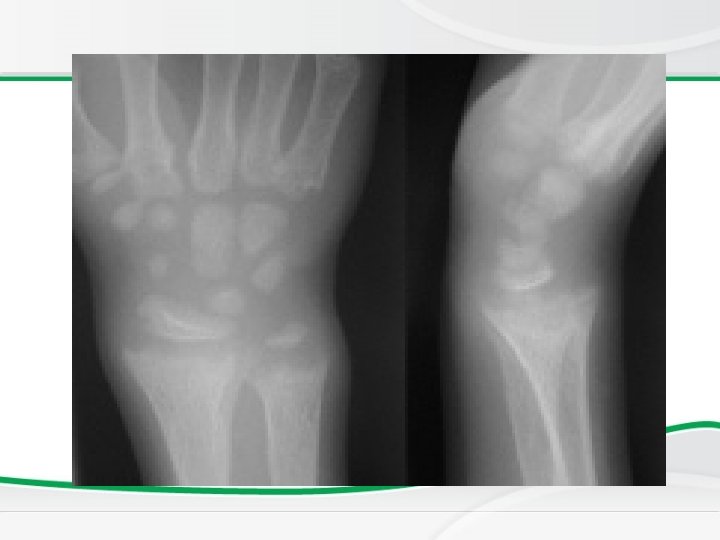

Investigations, • BASIC INVESTIGATIONS TO CONFIRM RICKETS • • Low or normal serum Ca Low phospherus High alkaline phosphatase X rays of ends of long bones at knees or wrists – Shows Widening, fraying, cupping of the distal ends of shaft. • Vit D level low • Parathyroid hormone high

Genu valgus Wrist cupping Tri radiate pelvis Looser’s zones Wrist widening Wide metaphysis

• Full term 1 year old boy who presented with afebrile tonic clonic convulsions. He has no chronic illnesses or medication. On examination he has no apparent dysmorphic features and his vital signs were normal. a. Describe an abnormality. b. List two important investigations to confirm your diagnosis. c. What is the most likely diagnosis?

• Full term 1 year old boy who presented with afebrile tonic clonic convulsions. He has no chronic illnesses or medication. On examination he has no apparent dysmorphic features and his vital signs were normal. a. Describe an abnormality. b. List two other important investigations to confirm your diagnosis. Answer: a. Bowing of legs b. 1. Serum calcium level, serum alkaline phosphatase, 25 Vitamin D level, hand x-ray 2. Possible diagnosis is nutritional Vitamin D deficiency.